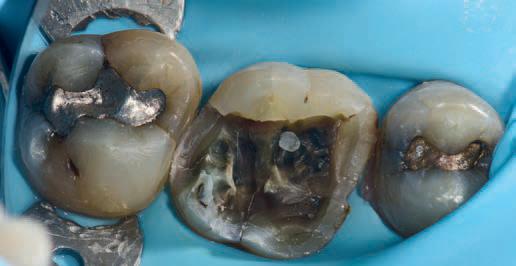

No teeth were tender to percussion. Tooth 26 reacted strongly to cold testing while the other teeth reacted normally. Tooth 26 tested positive to biting on damp gauze but the sensation did not linger. Both tooth 27 and 25 were negative to the bite test. The composite resin restoration in tooth 26 was removed under rubber dam and crack lines could be seen under the restoration (Fig. 1), with the most obvious running from the lingual to the centre of the tooth, and another from the mesiobuccal to the centre. A number of other minor cracks were visible, including one that ran under the buccal cusps (Fig. 1).

a core material for indirect restoration

Fig. 1

Fig. 4: Initial access showing existing cracks.